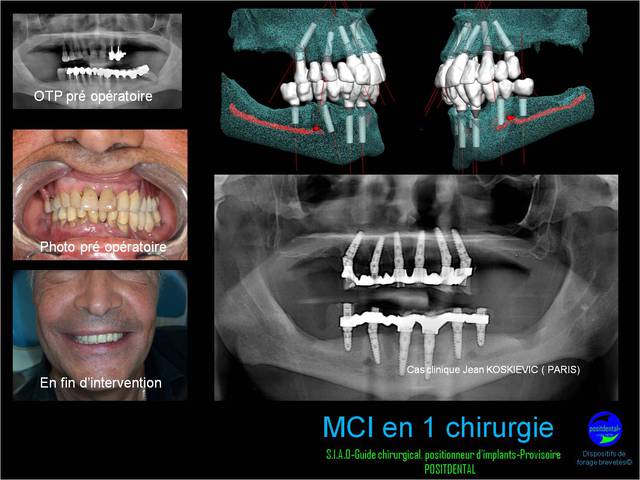

suite